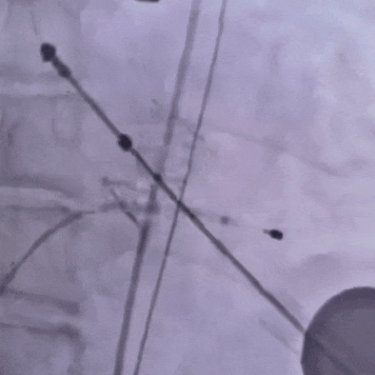

该技术是一种微创瓣膜植入手术,通过微创介入方式,经心尖小切口将人工瓣膜精准植入病变主动脉瓣位置,无需体外循环和正中开胸,从而大大降低手术风险。据李保军教授介绍,TA-TAVR术需在跳动的心脏上完成瓣膜释放,误差需控制在毫米级,对团队配合和操作精度要求极高。

在心外科、麻醉科、手术室等团队紧密配合下,术中通过DSA影像系统实时协同,从安置临时起搏电极、心尖部“荷包”缝合到瓣膜精准释放,整个过程有条不紊,复查超声提示:瓣膜位置良好,无瓣周漏,无反流,我院首例TA-TAVR顺利置入成功。术后一周,患者恢复良好,已康复出院。